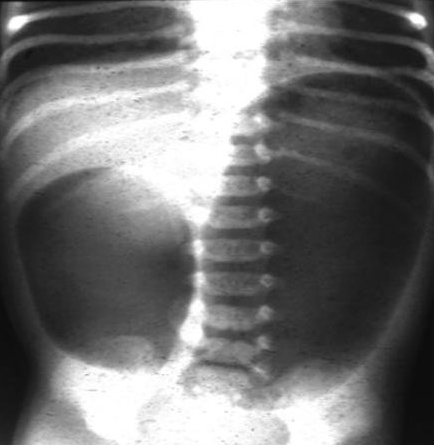

Radiografia abdominal exibindo padrão de gases com sinal da dupla bolha consistente com atresia duodenal

Do acervo de Dr. KuoJen Tsao; usado com permissão